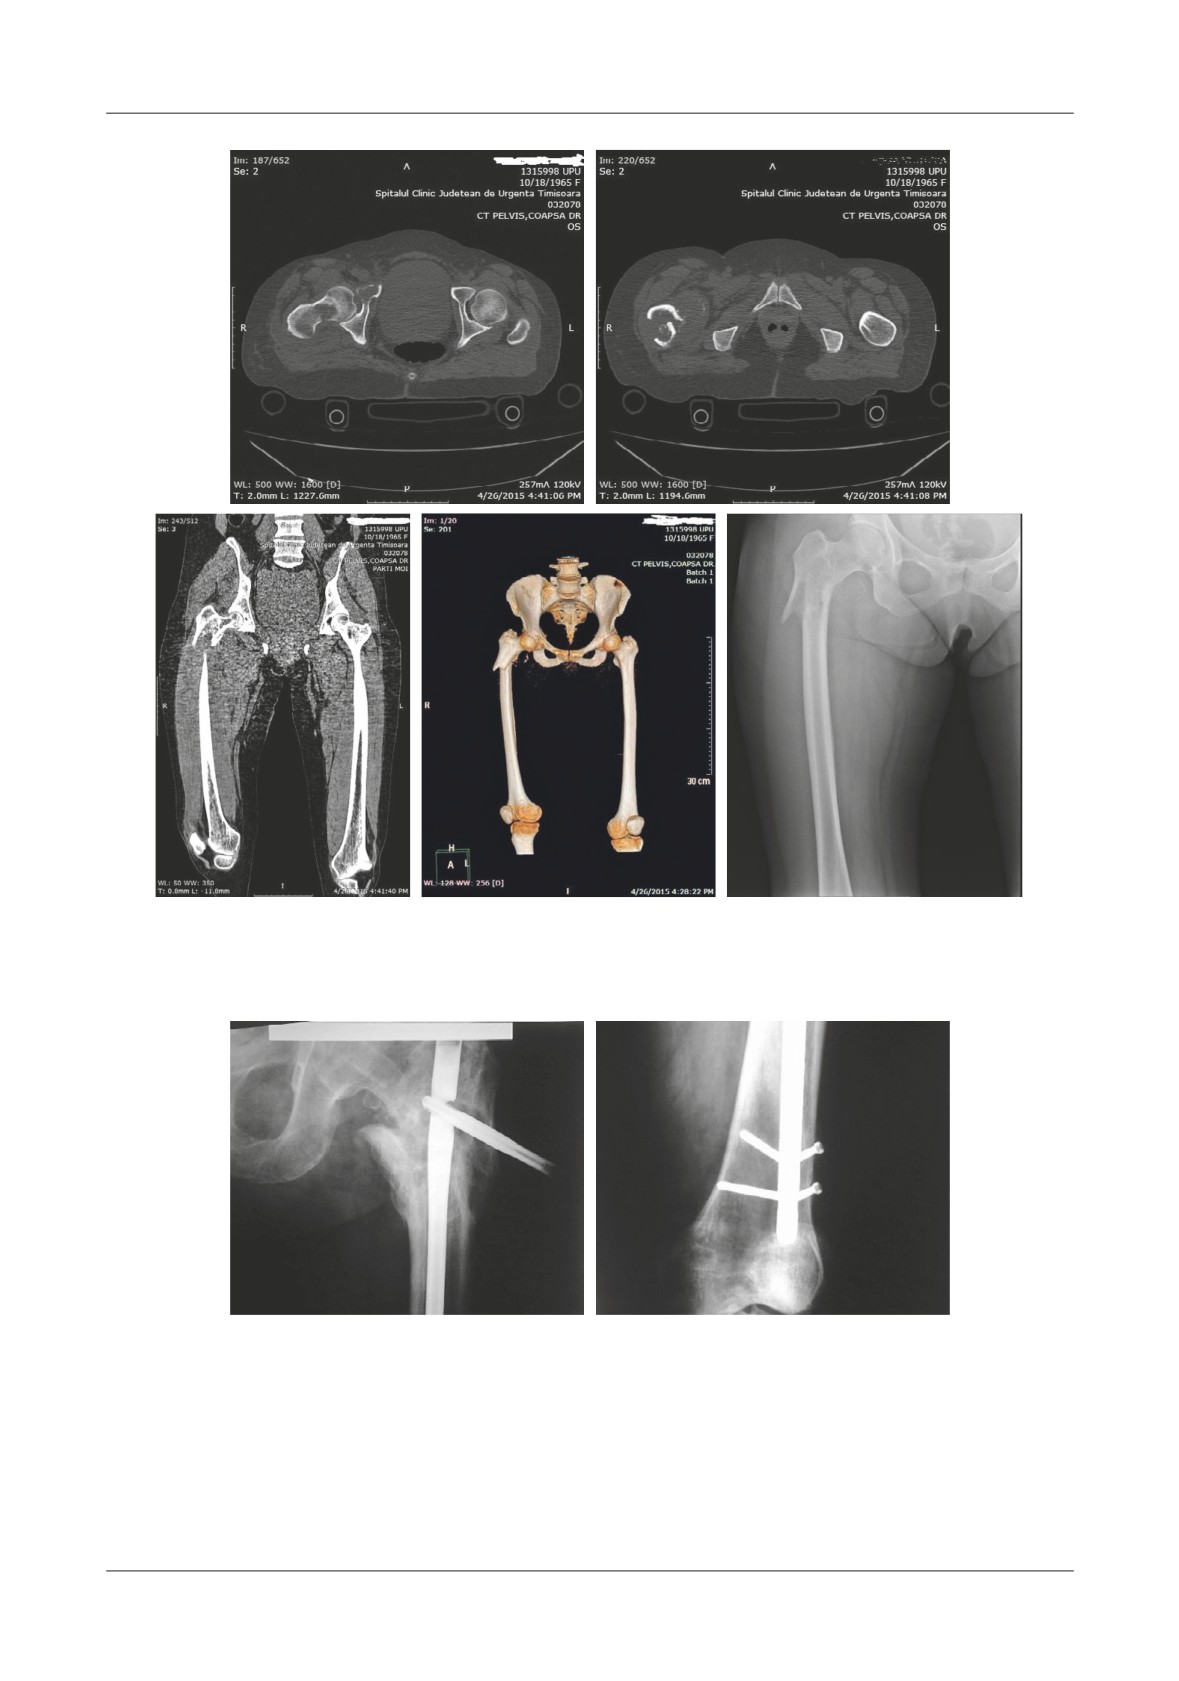

Figure 2. A,B. Axial CT images that reveal the lytic bone area from within the femoral neck as well as the zone

of the pathologic fracture. C. Coronal CT reconstruction shows the tumor mass that expands the muscles

surrounding the proximal femoral area. D. 3D CT reconstruction meant to carefully show if there are any

other fractures that expand distally. E. AP X-ray of the right coxo-femural joint

Figure 6. A. Initial AP X-ray of the pelvis which reveals the un displaced fracture. B. 2 weeks later the fracture has become displaced

and requires surgical care. C. Te postoperative X-ray reveals proper fixation of the implant and early mobilization is indicated